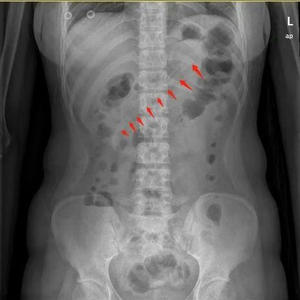

李小姐去东莞石碣医院求助医生,腹部X线检查显示,李小姐胃中的勺子长达17厘米。如果不取出,患者可能会出现消化道梗阻、出血和穿孔等并发症。医生赶紧安排李小姐入院治疗。

实施无痛麻醉后,在医生操作下,胃镜快速就位。通过胃镜,一进入胃腔就能看到一根长长的塑料勺子横跨在胃体至十二指肠球部。医生一开始选择用异物钳钳夹异物,但因为太大了无法夹住,给手术进行带来了一定难度。随后,她改用圈套器,尝试套住异物。但因异物两端顶住胃腔和十二指肠球腔,要想套住异物并不容易。经过不断地调整圈套的方向,终于套住了勺子合适的位置,顺着胃食管纵轴缓缓取出。

历经40分钟,一根长约17cm的粉色塑料勺子终于从胃内取出了。手术圆满结束后,患者家属悬着的一颗心也放下了,并向医务人员竖起大拇指点赞。

术后取出的约17厘米长的勺子医生提醒